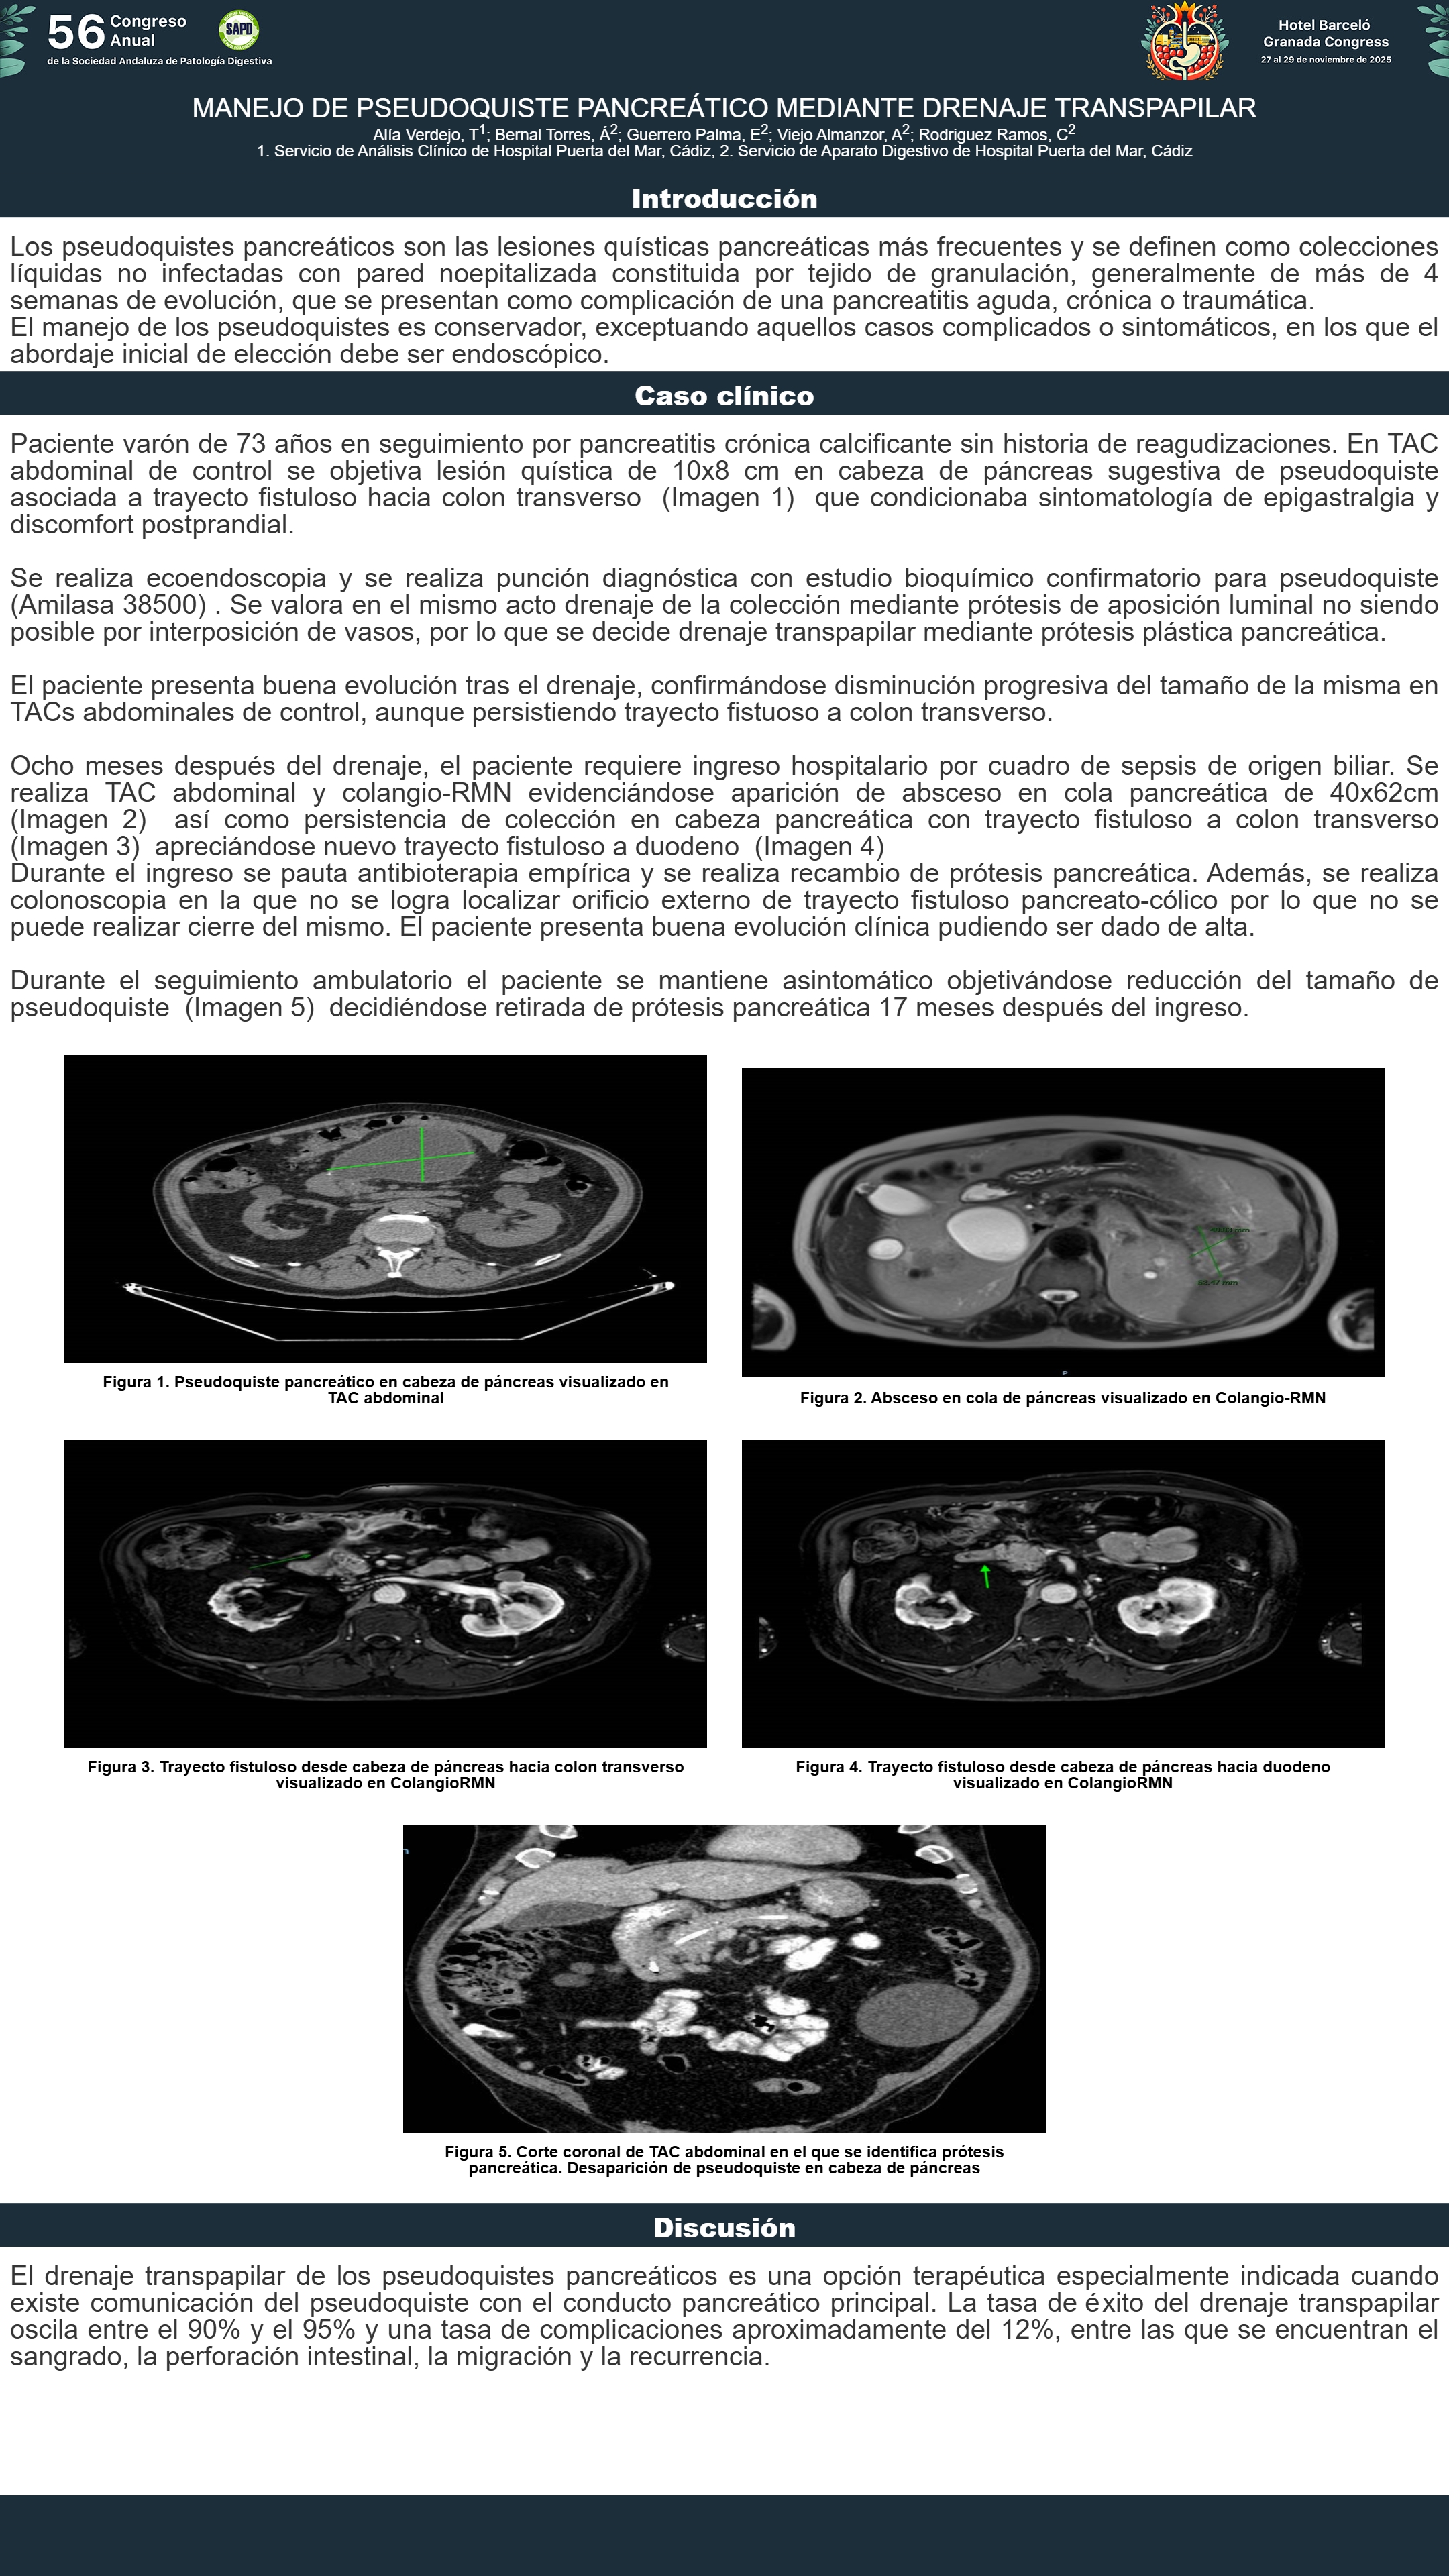

[CP-010] MANEJO DE PSEUDOQUISTE PANCREÁTICO MEDIANTE DRENAJE TRANSPAPILAR